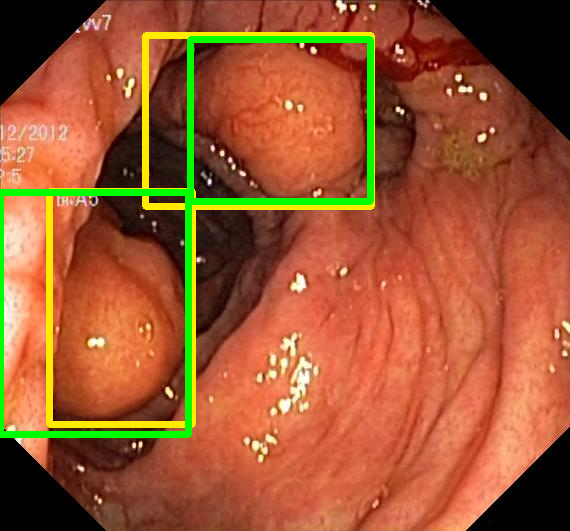

We evaluate the resulting object detection models using the test data, which is pre-processed in the same manner as the validation data, with AP@[.5:.95] (AP for conciseness), AP@.5 (AP5050{}_{50}start_FLOATSUBSCRIPT 50 end_FLOATSUBSCRIPT), and AP@.75 (AP7575{}_{75}start_FLOATSUBSCRIPT 75 end_FLOATSUBSCRIPT) computed for predicted bounded boxes with a confidence score \geq0.05. For all metrics, a higher value indicates better performance. The results are presented in Table VI, and some examples for predicted bounding boxes with a confidence score \geq0.5 are shown in Fig. 1.

RN-HK-MC RN-HK-BT RN-IN-MC RN-IN-BT RN-IN-SL RN-NA-NA Refer to caption Refer to caption Refer to caption Refer to caption Refer to caption Refer to caption Refer to caption Refer to caption Refer to caption Refer to caption Refer to caption Refer to caption VT-HK-MC VT-HK-MA VT-IN-MC VT-IN-MA VT-IN-SL VT-NA-NA Refer to caption Refer to caption Refer to caption Refer to caption Refer to caption Refer to caption Refer to caption Refer to caption Refer to caption Refer to caption Refer to caption Refer to caption

Figure 1: Targets (yellow bounding boxes) and predictions (green bounding boxes) for two randomly selected instances of the Kvasir-SEG test set. For conciseness, we denote ResNet50s with RN, ViT-Bs with VT, Hyperkvasir-unlabelled with HK, ImageNet-1k with IN, MoCo v3 with MC, Barlow Twins with BT, MAE with MA, supervised pretraining with SL, and no pretraining with NA-NA.